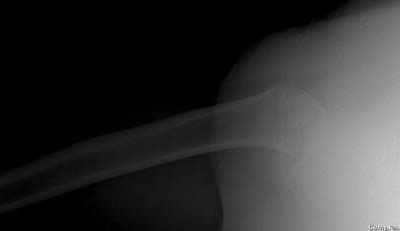

Да. У нас довольно скромный опыт такого остеосинтеза (по 2 случая - плечо и наружная лодыжка), дошли до использования самого простецкого троакара, через который мы сверлим кость и вводим 6 мм стержни, когда накладываем аппарат. Соответственно, в качестве забойника отлично работает любой стержень от аппарата Илизарова. Еще из наших туземных особенностей - страшная любовь к спицевым дистракторам, поэтому делали в нем. Результат у этой дамы неизвестен, т.к. она из области и уехала рожать сразу после остеосинтеза, сейчас прошло больше 5 месяцев...